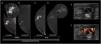

In males with gynecomastia, detecting DCIS on mammography can be challenging.19 Microcalcifications are seen less likely in male breast cancers, possibly due to the involuted ductal structure.4 When present, these calcifications often have a benign or nonspecific appearance 19 (Fig. 8). Additionally, if invasive carcinoma is present, parenchymal opacity or distortion may be seen.4 DCIS normally presents a non-mass enhancement on the recombined images of CEM (Fig. 9).

47-year-old male presented with left breast growth for 5 months and unilateral clear discharge. On the low energy images (A, C), a focal asymmetry of the entire upper-external quadrant of the left breast with associated diffuse calcifications are seen. On the recombined images (B, D), a segmental non-mass enhancement is observed. Sonographically (E), the lesion corresponds to a heterogeneous mass. 14G core needle biopsy proved DCIS (F). Histology after mastectomy confirmed pure DCIS with no invasive component.

The findings on ultrasound for DCIS in males are non-specific and not well-documented in the literature. However, coexistent invasive ductal carcinoma foci may be visualized as a mass or distortion.4